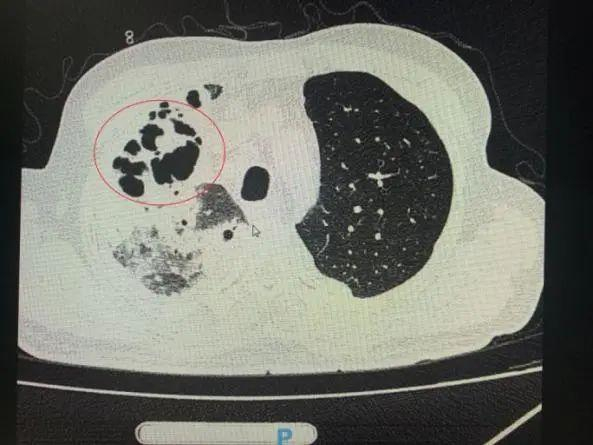

番禺院区呼吸内科何梦璋主任接诊后,对钟叔进行详细检查。此时,钟叔的病情已经十分危急,由于不能自主呼吸,他带上了无创呼吸机辅助呼吸治疗。看到钟叔胸片时,医护人员头皮也一阵发麻,胸部CT可见双肺多发的炎症浸润、双肺多发空洞。通俗来说,钟叔的肺部已经被病原体蚕食,啃出无数个大小各异的洞!可怕的是,这种病变对肺功能的破坏是永久性、不可恢复的。根据钟叔病史以及胸部CT结果,最终诊断为“吸入性肺脓肿”

钟叔的肺部被病原体蚕食,啃出无数个大小各异的洞。